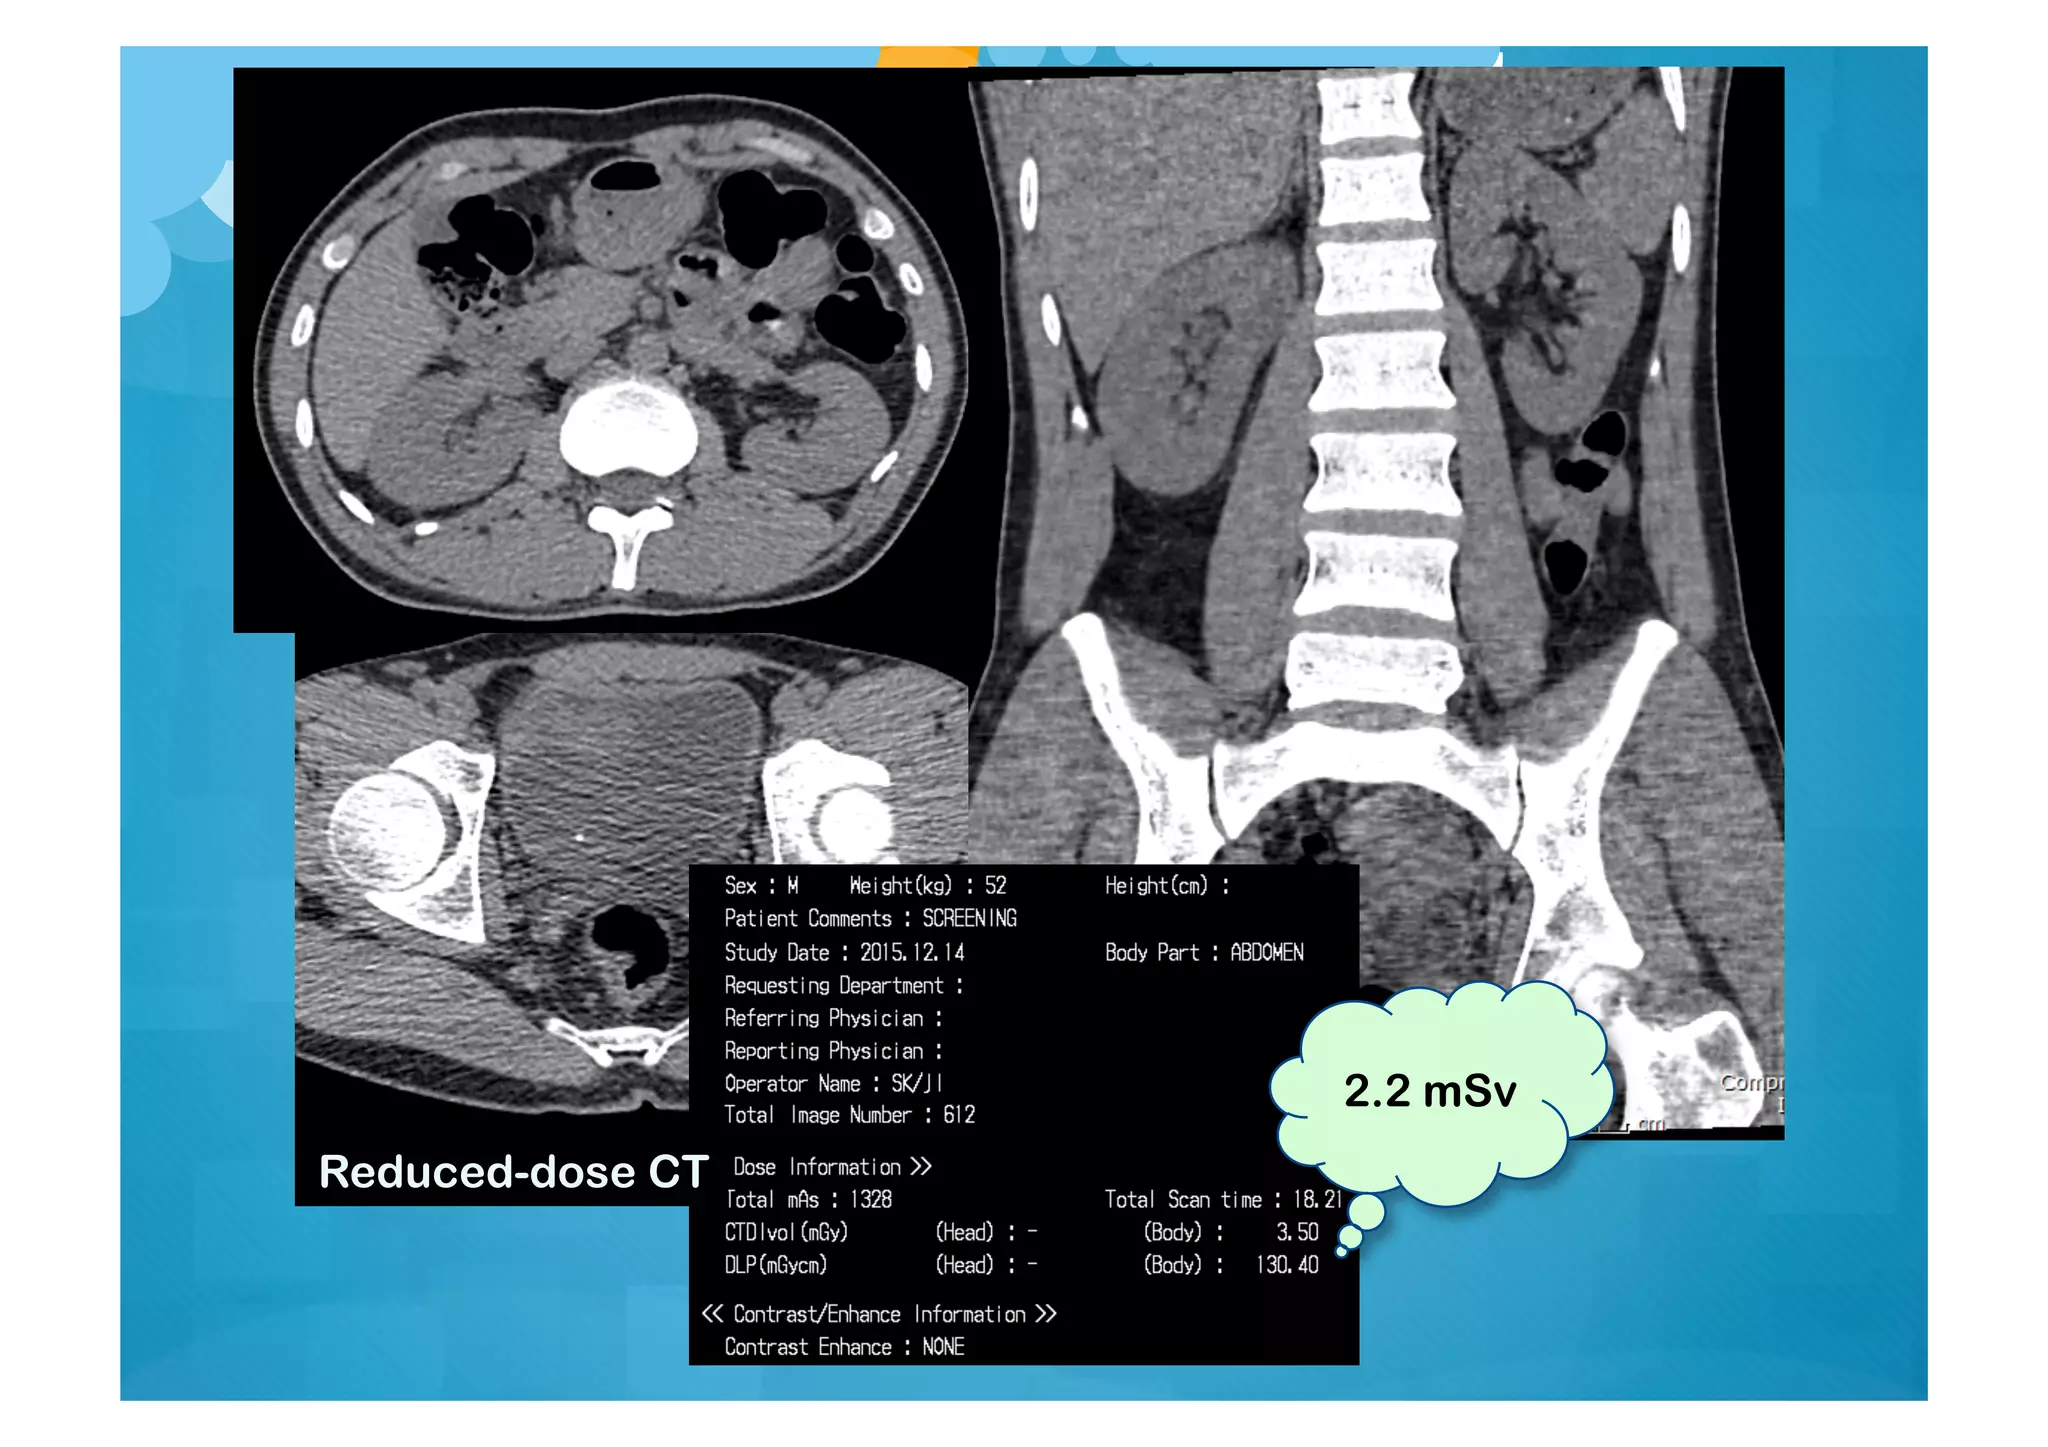

Stone CT Radiation Dose

Stone CT Radiation Dose:

How Low Can We Go?

Moore CL, et al. Ann Emerg Med 2015;65:189

N=201

Prospective, head-to-head comparison standard v reduced-dose CT

Two groups: BMI <30 v. BMI >30

2.2 mSv

Reduced-dose CT

Initial CT

F/U CT (known

stone)

Can accept more

noise to reduce dose

8.3 mSv

3.7 mSv